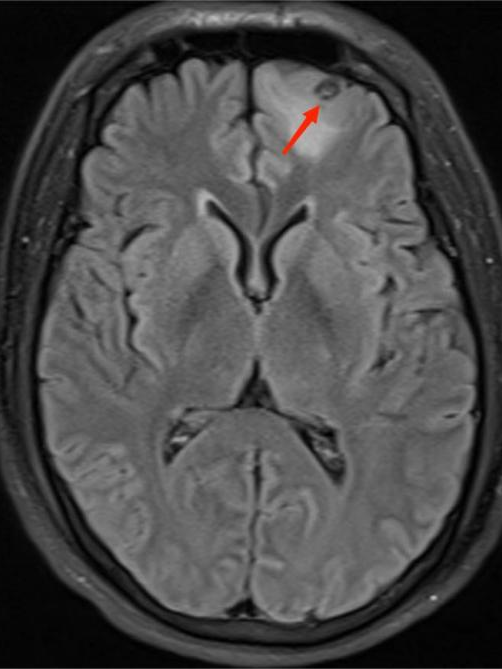

得到这条线索后,ICU 医生立即为李先生进行一系列脑部检查。最终,李先生头颅 MR 显示其脑内有寄生虫感染!明确诊断为脑囊虫病!